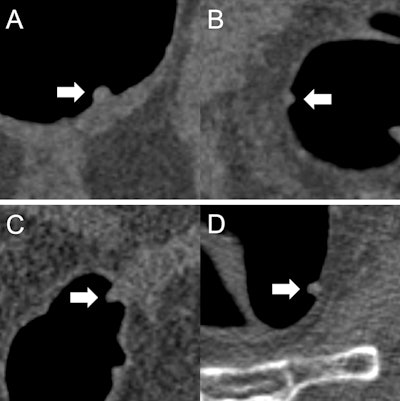

(A) A 9 mm tubular adenoma that was classified by all readers as "polypectomy: yes." The initial recommendation was confirmed based on the prediction "adenomatous" of the AI model. (B) A 6 mm hyperplastic polyp that was classified by all readers as "polypectomy: no." The initial recommendation was confirmed based on the prediction "nonadenomatous" of the AI model. (C) An 8 mm tubular adenoma that was classified by three readers as "polypectomy: no." The initial recommendation was corrected by all three readers based on the prediction "adenomatous" of the AI model. (D) A 7 mm hyperplastic polyp that was classified by two readers as "polypectomy: yes." The initial recommendation was corrected by both readers based on the prediction "nonadenomatous" of the AI model. All figures courtesy of Dr. Sergio Grosu et al and European Radiology.